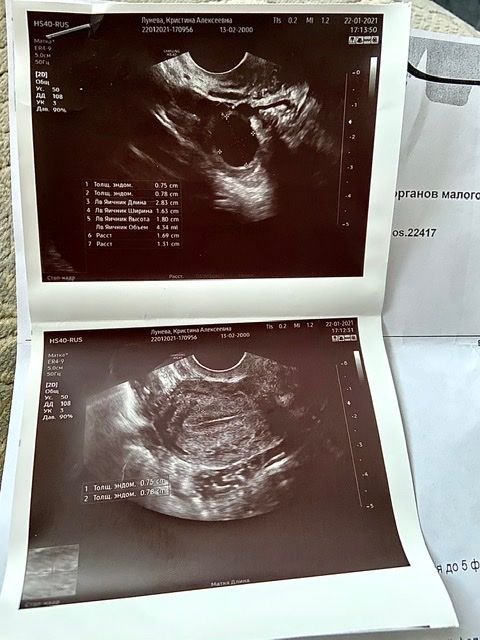

Фазы цикла на узи

Фазы цикла на узи 117 фото